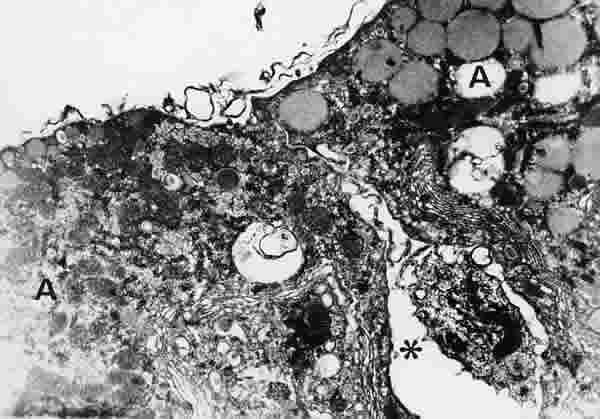

Figura 35

BIOPSIA EN UN PACIENTE CON SS1-GRADO II. LAS CÉLULAS ACINARES (A) ESTÁN BASTANTE SEPARADAS ENTRE SÍ (*). LA SUPERFICIE CELULAR NO POSEE MICROVELLOSIDADES. LAS CÉLULAS TIENEN UN MODERADO NÚMERO DE ORGÁNULOS SUBCELULARES PERO CON ESCASOS GRÁNULOS DE SECRECIÓN (gs). MICROSCOPIA ELECTRÓNICA. MAGNIFICACIÓN ORIGINAL X8000.